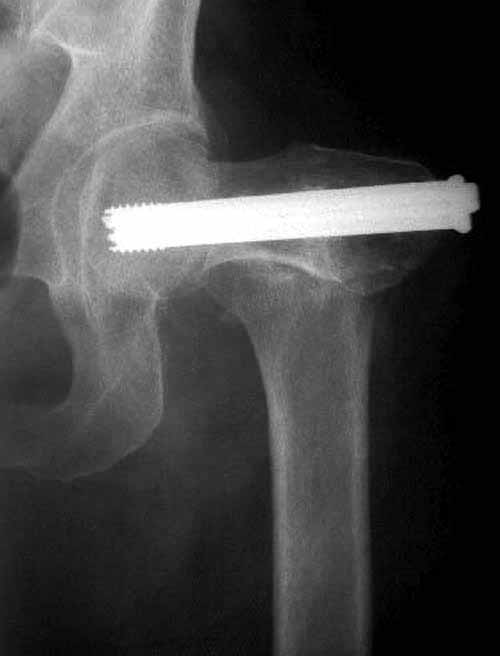

Пациентка Ш. 76 лет, 11 дней назад прооперирована по поводу вколоченного субкапитального перелома шейки левой бедренной кости, 3-мя канюлированными винтами. Вчера пациентка упала в палате. И вот результат- подимплантатный подвертельный перелом левой бедренной кости. Уважаемые коллеги, пожалуйста посоветуйте какой метод дальнейшего лечения предпринять дальше.Соматически пациента повышенного питания, страдает варикозной болезнью нижних конечностей.Из предложенных вариантов коллег - целллокастовая укороченная кокситная повязка, скелетное вытяжение сроком на 40-45 суток - отпали сразу, так как необходимо активизация пациентки.На данный момент рассматриваем следующие варианта реостеосинтеза:(наличие технических возможностей) 1. Длинная Gamma 3 Stryker (с предварительной интраоперационной фиксацией головки спицами).2. Трохантерный штифт DePuy с 2-мя метафизарными винтами в проксимальном отделе, (также с интраоперационной фиксацией головки спицами. Очень настораживает стабильность фиксации с проксимальном отделе с связи с выборкой костной ткани ранее находящимися там канюлированными винтами. Сейчас пациентка находится на скелетном вытяжении, с дисциплинирующим грузом. Операция планируется после праздников. Заранее извиняемся за качество и неполное соответствие проекций на R-ммах (R-служба отдельная песня). При интраоперационном ЭОП-контроле винты в аксиальной проекции разнесены по шейке.

Редукция отличная, а вот с фиксацией есть проблемы:

1. винты расположены не в лучшем положении:

два в нижней части шейки. Более стабильная структура как раз обратная: два шурупа в проксимальной части шейки , и не дальше центральной части головки, иначе есть риск пенетрации. дистальный винт мог бы быть выше уровня малого вертела. Его дистальное расположение описано с увеличенным риском послеоперационного перелома.

Согласен с Николаем, винты распоожены так, чтобы эту "мину" заложить. И два внизу, и не должны, даже если один он там, они входить ниже уровня малого вертела, это резко повышает риск подвертельного перелома. Что до остеосинтеза - учитывая 76 лет, более подходящей представляется большего диаметра винт в шейке, то есть гамма.